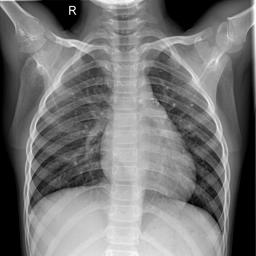

Large numbers of labeled medical images are essential for the accurate detection of anomalies, but manual annotation is labor-intensive and time-consuming. Self-supervised learning (SSL) is a training method to learn data-specific features without manual annotation. Several SSL-based models have been employed in medical image anomaly detection. These SSL methods effectively learn representations in several field-specific images, such as natural and industrial product images. However, owing to the requirement of medical expertise, typical SSL-based models are inefficient in medical image anomaly detection. We present an SSL-based model that enables anatomical structure-based unsupervised anomaly detection (UAD). The model employs the anatomy-aware pasting (AnatPaste) augmentation tool. AnatPaste employs a threshold-based lung segmentation pretext task to create anomalies in normal chest radiographs, which are used for model pretraining. These anomalies are similar to real anomalies and help the model recognize them. We evaluate our model on three opensource chest radiograph datasets. Our model exhibit area under curves (AUC) of 92.1%, 78.7%, and 81.9%, which are the highest among existing UAD models. This is the first SSL model to employ anatomical information as a pretext task. AnatPaste can be applied in various deep learning models and downstream tasks. It can be employed for other modalities by fixing appropriate segmentation. Our code is publicly available at: https://github.com/jun-sato/AnatPaste.